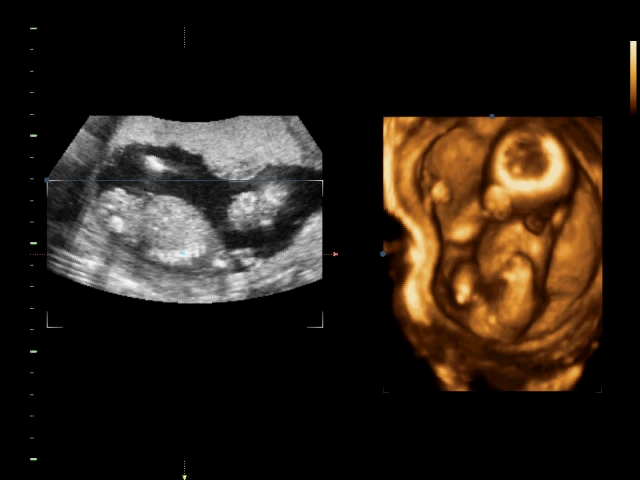

Пол на 14 неделе беременности по узи

Пол на 14 неделе беременности по узи 88 фото